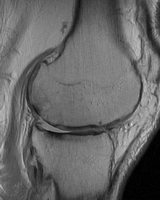

MRI ile osteoartrit erken evrede teşhis edilebilir!

NYU Langone Tıp Merkezi Ortopedik Cerrahi ve Radyoloji Departmanı araştırmacıları, MRI teknikleri ile eklem kıkırdak mikro yapısındaki küçük değişikliklerin saptanabileceğini ve MRI’ın erken başlangıçlı osteoartrit için tanısal bir araç olarak kullanılabileceğini saptadılar. Osteoartritli hastaları belirlemek için bu tekniklerden yararlan hekimler, erken teşhis ile hastaların eklem yapısını uzun süreli koruyabilir.

Klinik uygulamada standart, eklem ağrısı veya bilinen artriti olan hastalarda kıkırdak kalitesini değerlendirmek için, kıkırdağın morfolojik bütünlüğünü inceleyen konvansiyonel MRI tekniğinin kullanılmasıdır. Laboratuarda ise; radyoloji uzmanları, ortopedi cerrahları ve romatologlar osteoartritin neden olduğu kıkırdak hasarını değerlendirecek MRI teknolojisini ve biyokimyasal görüntüleme yöntemlerini geliştirmek için işbirliği yapar. Hasarlı kıkırdak dokusunda su ve kolajen molekülü konsantrasyonunda, mikro ve makro kolajen yapısında ve özel bir protein olan glikozoaminoglikan konsantrasyonlarında küçük çaplı değişimler görülür. Yapılan çalışma bulguları, genç hastalarda MRI teknikleri ile erken başlangıçlı osteoartritin teşhis edilebileceğini ortaya koymuştur. Bu, hastalığın progresyonunun durdurulması için erken tedavi anlamına gelir.